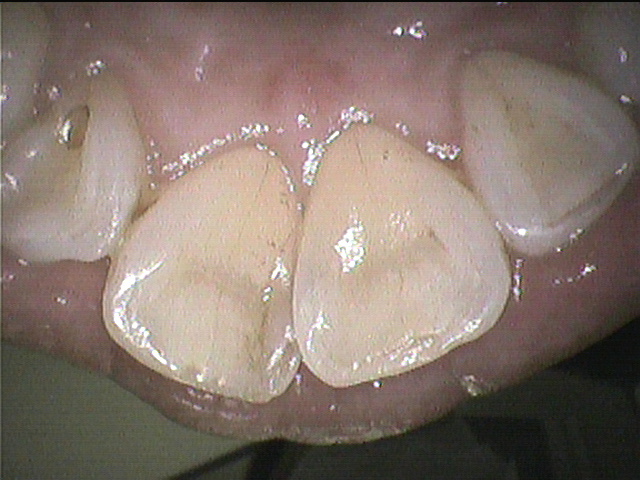

後

クリーニングは3ヵ月~半年に一度がおすすめですが、

歯周病傾向がある方やステインが気になる方は2ヵ月に一度をおすすめする場合もあります。